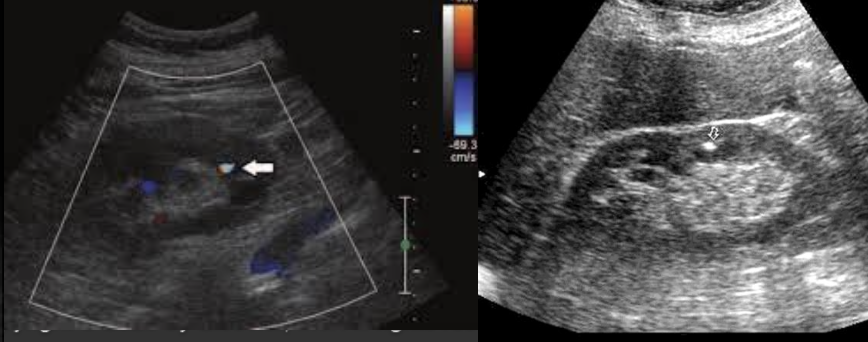

Pseudoaneurysm → rupture from intima layer contained in deeper layers of artery wall

clinical hx: older male, post-catheterization/surgery, trauma

s/sx: acute pulsatile mass, expending mass, pain with bruising, decreased hematocrit, ± increased WBC with mycotic/infected pseudoaneurysm → symptoms appear within hours/days

2D US presentation: heterogenous, pulsating central structure with internal swirling of brighter echogenicity

color doppler: “yin-yang” sign, “to and fro” PW waveform

DDX: hematoma (hypoechoic intraluminal echoes, but not color flow or neck connecting), true aneurysm (wide rather than narrow neck continuous w/ artery, chronic rather than acute)